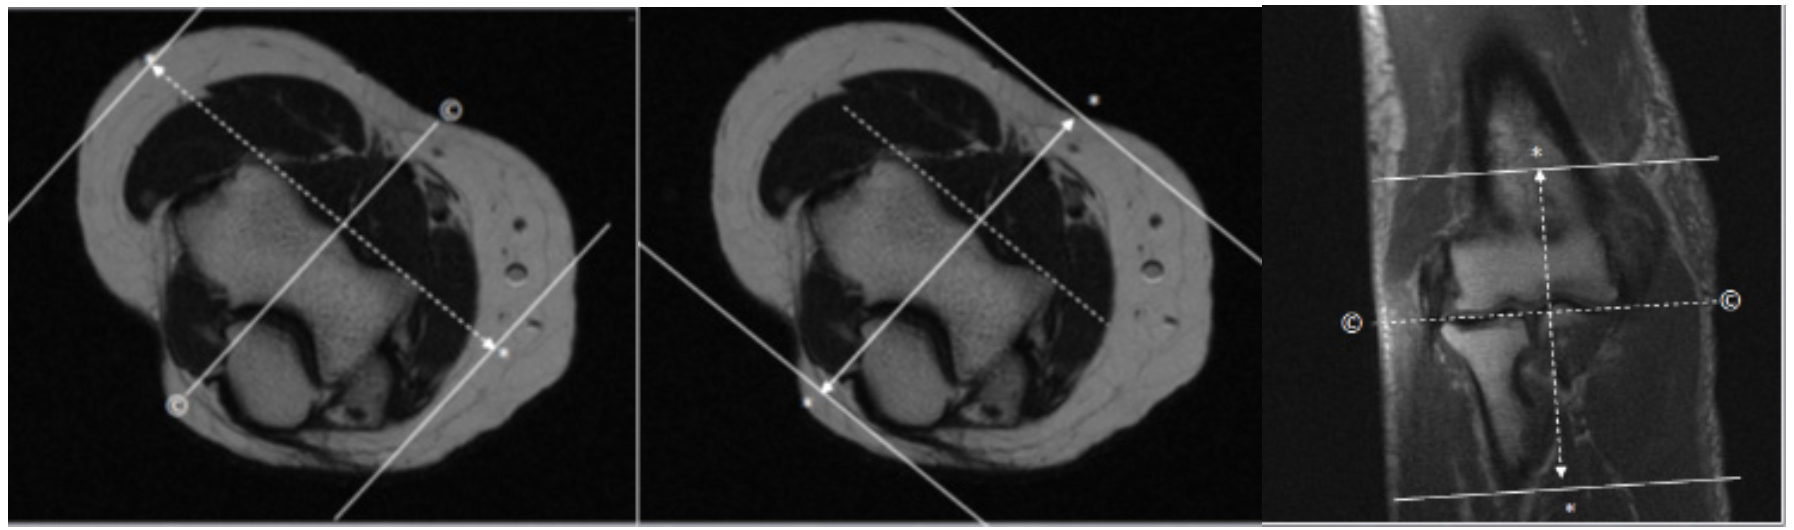

| SAG | T2 STIR | TSE | 3mm | 0.5mm | STIR | 14cm | Angle to Distal Humeral Condyles |

| COR | T2 STIR | TSE | 3mm | 0.5mm | STIR | 14cm | Angle to Distal Humeral Condyles |

| COR | T1 | TSE | 3mm | 0.5mm | None | 14cm | Angle to Distal Humeral Condyles |

| AX | T1 SPIR | TSE | 3mm | 0.5mm | SPIR | 14cm | Angle to Distal Humeral Condyles |

| SAG | T1 SPIR | TSE | 3mm | 0.5mm | SPIR | 14cm | Angle to Distal Humeral Condyles |

| COR | T1 SPIR | TSE | 3mm | 0.5mm | SPIR | 14cm | Angle to Distal Humeral Condyles |